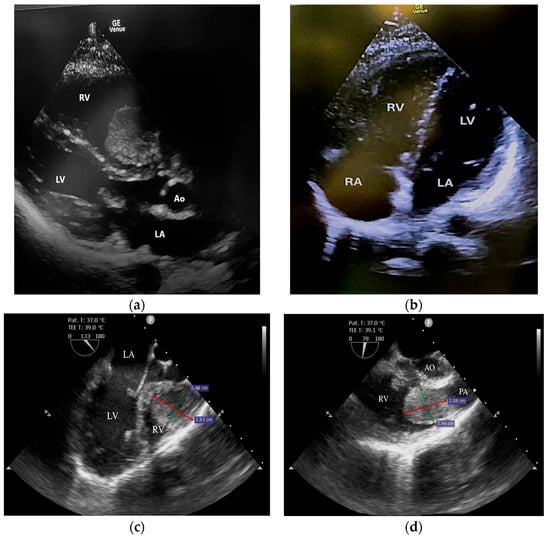

Swinging Mass Through the Pulmonary Valve: A Rare Case of Right Ventricular Myxoma

Primary cardiac tumors are rare, with an estimated incidence of 0.001% to 0.3% in autopsy series. Most are benign, the most common being cardiac myxomas, which typically originate in the left atrium. Right ventricular myxoma is among the rarest primary cardiac tumors, and its true incidence is difficult to determine, as most data come from isolated case reports. This paper aims to report a case of right ventricular myxoma in a young woman with a history of childhood malignancy and to discuss the possible association between the two conditions. Echocardiography, thoracic computed tomography (CT), and pulmonary CT angiography were used to assess the presence, location, and size of the tumor. The definitive diagnosis was established by histopathological examination. A 34-year-old woman, with a past medical history of acute lymphoblastic leukemia (ALL) in childhood, presented with a dry cough and exertional dyspnea persisting for three weeks. Transthoracic echocardiography revealed a mass located in the right ventricular outflow tract (RVOT), attached near the tricuspid valve and intermittently prolapsing into the pulmonary trunk. CT imaging confirmed the presence of the tumor in the RVOT and the main pulmonary artery. Because of the high risk of massive pulmonary embolism, the patient underwent urgent surgical excision of the tumor. Histopathological analysis confirmed the diagnosis of cardiac myxoma. The postoperative recovery was uneventful, and the three-month follow-up showed no recurrence or signs of pulmonary embolism. The patient’s history of ALL raised the question of a possible association; however, a review of the literature revealed no previously reported link. In conclusion, right ventricular myxomas are extremely rare. The occurrence of cardiac myxoma in this patient following childhood ALL appears to be incidental. Further research is needed to determine whether ALL survivors have an increased predisposition to subsequent cardiac tumors. Full article

Show Figures

Figure 1